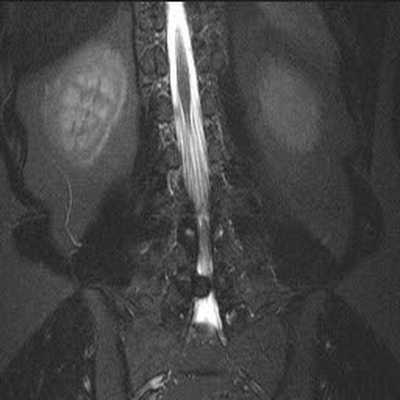

МРТ позвоночника. Сагиттальная Т2-взвешенная МРТ, срединный срез поясничного отдела. Показана нумерация позвонков, измерения позвоночного канала (черная линия). Т- дуральный мешок с ярким ликвором. L- желтая связка. Sacrum - крестец. D - межпозвоночный диск. Голубым выделен остистый отросток, желтым - тело позвонка, Голубые точки - ход корешков.

После того, как появилась ясность в способе получения МРТ изображений позвоночника, надо понять какие анатомические структуры видны. Счет позвонков ведется разными способами - сверху от зубовидного отростка С2 (осевой позвонок), от бифуркации трахеи Т5 ( пятый грудной, с погрешностью на 1 позвонок) или снизу от L5 (последний поясничный), также не исключена погрешность на 1 позвонок в связи люмбализацией или сакрализацией. Анатомия позвоночника в МРТ изображении представлена в нашей другой статье. На серии сагиттальных Т2-взвешенных МРТ позвоночника видны асе основные структуры, причем удается проследить ход корешков конского хвоста. В поясничном отделе он идет под углом вниз и выходит через межпозвоночное отверстие нижележащего позвонка. Аксиальные (поперечные) МРТ срезы всегда делаются вдоль межпозвоночного диска, то есть с учетом нормальных или патологических изгибов позвоночника. Они наиболее удобны для оценки состояния дугоотростчатых суставов. При МРТ позвоночника в поперечной плоскости МРТ срезы часто делают на разных уровнях для лучшей визуализации состояния корешков по их ходу - в дуральном мешке, затем боковом кармане дурального мешка, далее в межпозвоночном отверстии и, наконец, после выхода из него. Таким образом, в поперечном МРТ срезе позвоночника через межпозвоночное отверстие на поясничном уровне можно видеть отрезки сразу двух корешков - вышележащего на выходе из отверстия, и нижележащего в боковом кармане.